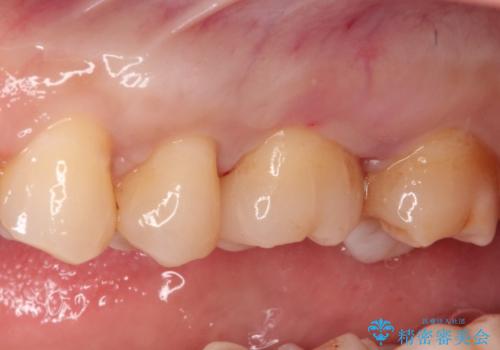

- 矯正終了後にメタルフリーの治療を希望された患者様です。

セラミックインレーにて修復治療を行なっております。

セラミックインレーのセット時にはラバーダムを用い防湿に気をつけて処置をしております。